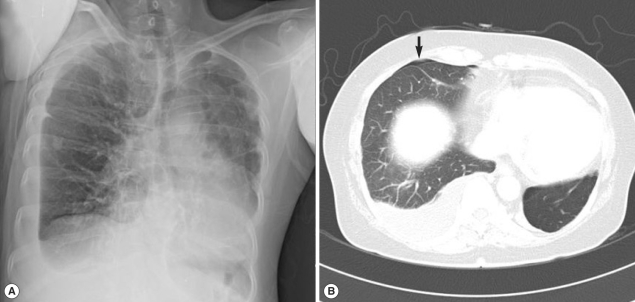

A 26-year-old woman (the daughter of cases 1 and 2) visited our hospital. The woman had previously been advised to undergo an examination because of her parents' diagnoses; however, because of time constraints, she was unable to visit our hospital until approximately 1 month after our initial recommendation. Recently, she had experienced general myalgia, vague night fever, and pleuritic pain. Approximately 4 to 5 days after her initial symptoms had developed, the woman noticed palpable subcutaneous nodules (5 to 10 cm in diameter) in her left flank. She said that she also had eaten Kejang with her parents. Auscultation revealed decreased breathing in the lower lung zone. A physical examination yielded no other specific findings. A CBC revealed WBC level of 28,000/mm3, hemoglobin level of 13.0 g/dl, platelet level of 313,000/mm3, AEC of 19,470/mm3, and ESR level of 90 mm/hr. Other laboratory tests revealed no abnormal findings. In simple chest x-ray, there was bilateral pleural effusion in both lung fields (Fig. 3A). In chest CT, bilateral pleural effusion with multiple patchy consolidations with focal bronchiectasis was observed (Fig. 3B). In abdominal CT, multiple low attenuated lesions in the liver and spleen were shown; they were suspected as eosinophilic abscesses caused by parasite infections. We performed stool examination and ELISA. We were unable to detect parasite eggs in the stool sample; however, ELISA results indicated the presence of Paragonimus and Clonorchis antibodies, and the total serum IgE level was 128 kU/L. The patient was also treated with praziquantel (25 mg/kg, 3 times daily for 2 days). All symptoms including pleuritic pain and subcutaneous nodules were resolved after the treatment, and the patient's AEC was decreased.

Fig. 3

Simple chest x-ray and CT findings in case 3. (A) Bilateral pleural effusion with focal patchy areas of increased opacity is seen in the lower upper and middle lung. (B) Bilateral pleural effusion with multiple patchy consolidations is seen (arrow).

Fig. 3 Simple chest x-ray and CT findings in case 3. (A) Bilateral pleural effusion with focal patchy areas of increased opacity is seen in the lower upper and middle lung. (B) Bilateral pleural effusion with multiple patchy consolidations is seen (arrow).